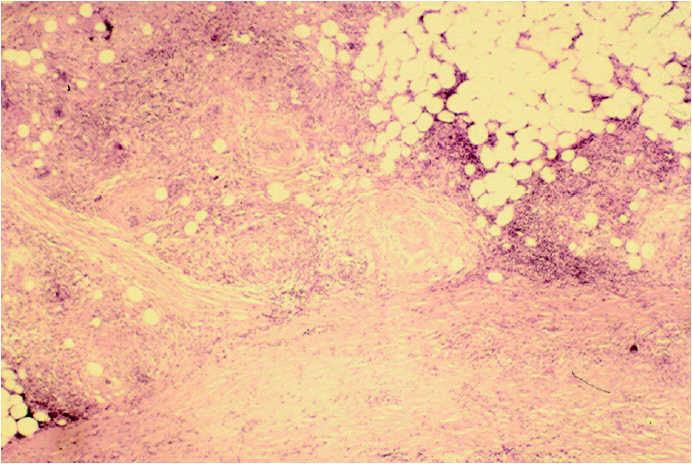

Un varón de 65 años, sin antecedentes personales ni familiares de interés que consultó por múltiples nódulos asintomáticos, de 8 meses de evolución. El inicio del cuadro coincidió con una caída accidental (fig. 1). En la exploración física presentaba 6 nódulos, localizados en el tercio distal de la cara de extensión de ambos brazos y zona suprarrotuliana izquierda, cuyo tamaño oscilaba entre 1 y 4 cm. Las lesiones estaban bien delimitadas, de consistencia pétrea y coloración de la piel normal, fácilmente desplazable sobre planos profundos. De forma llamativa adoptaban una morfología alargada.

Fig. 1.--Las lesiones nodulares adoptaban configuración alargada tras biopsia cutánea.